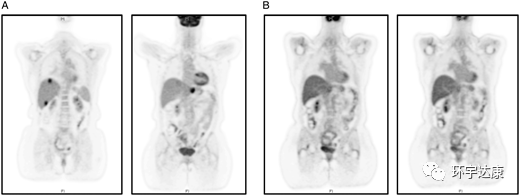

61岁的M女士被确诊为胰腺导管癌,胰腺体内有一个2.5cm的肿块,肝脏有1.2cm的转移病灶,基因检测发现NTRK1基因融合阳性,在接受拉罗替尼治疗后,胰腺和肝脏的病灶都明显缩小。

图2。

PET-CT扫描:(A)治疗前(B)拉罗替尼治疗后